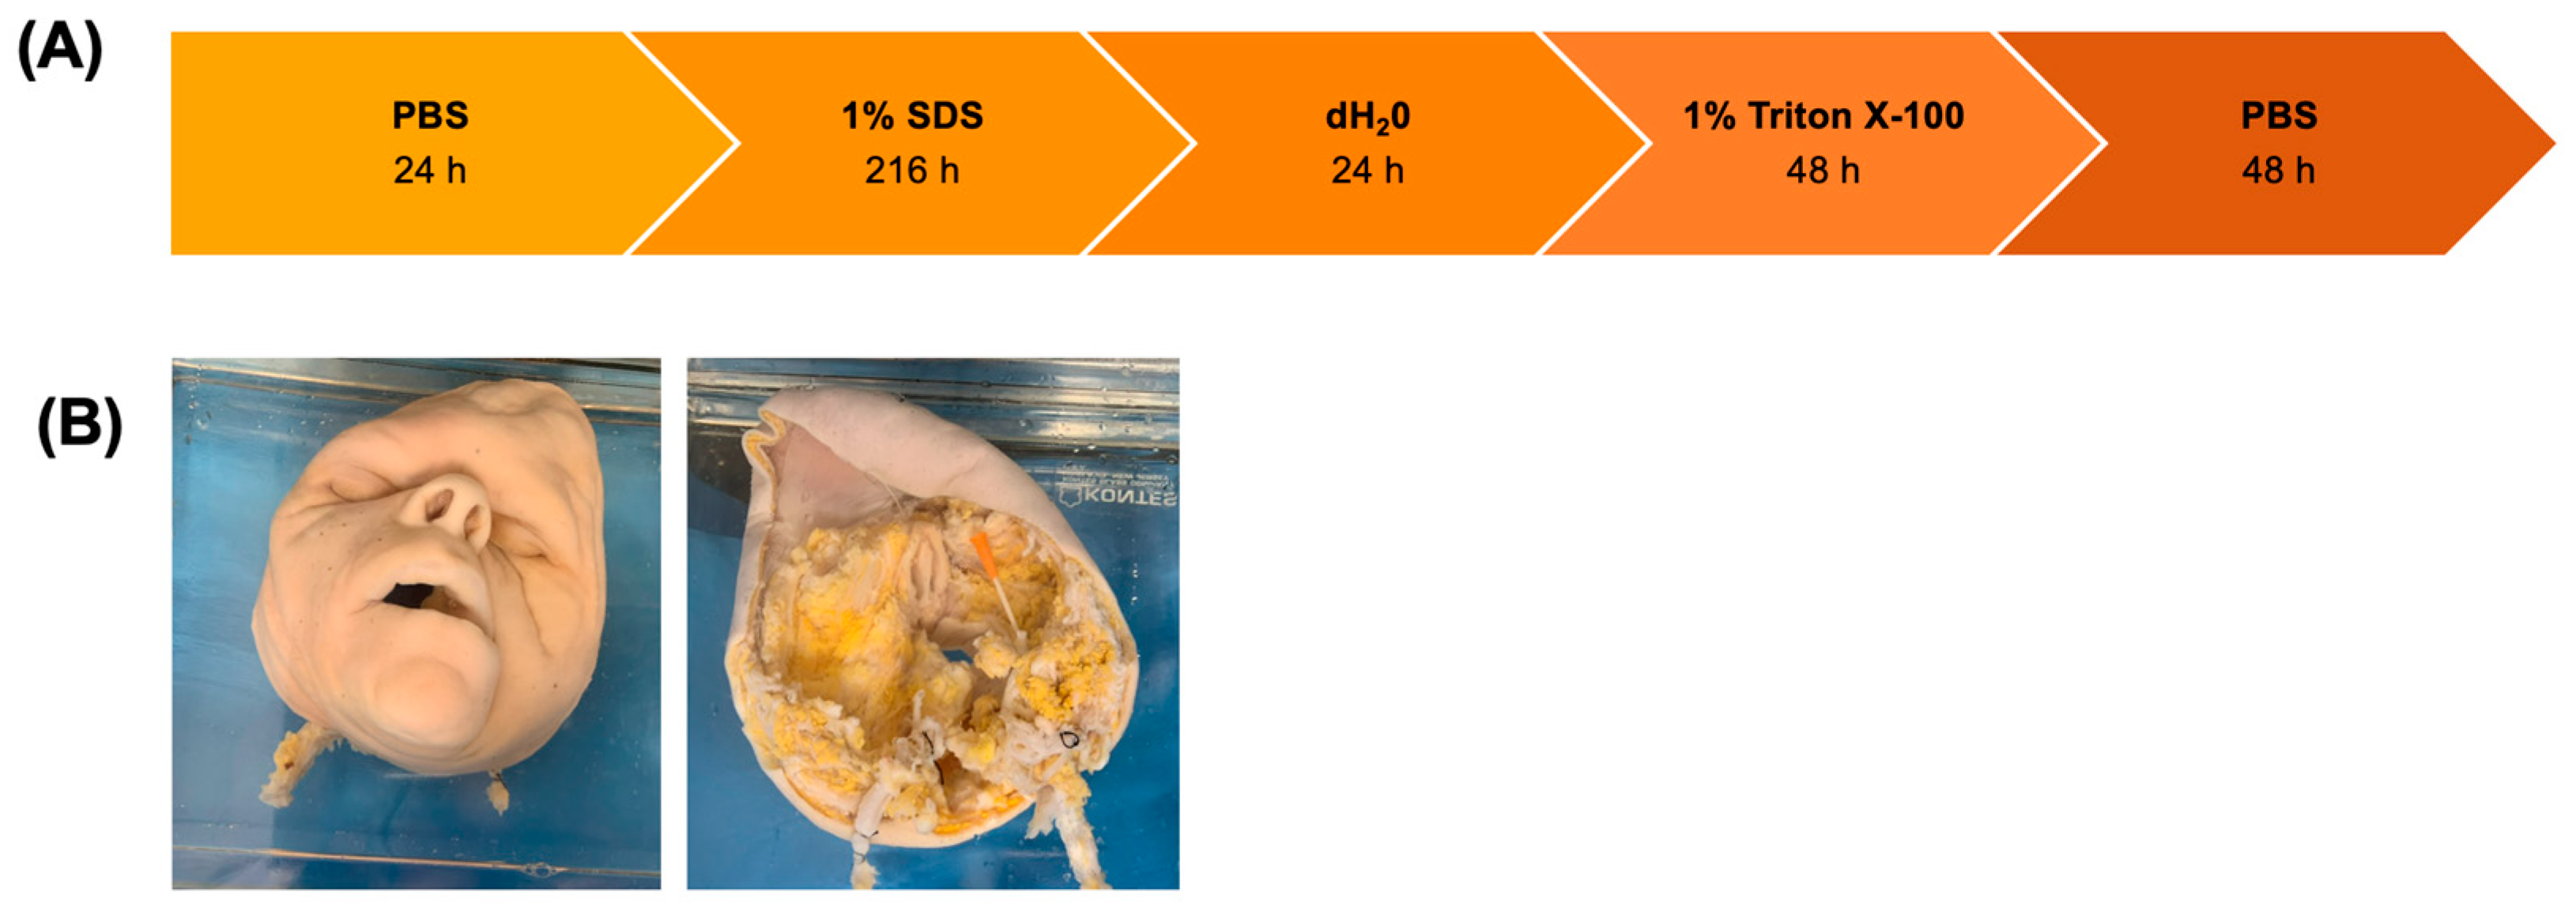

2.2. Decellularization of Facial Grafts

3.1. Assessment of Decellularization Efficiency